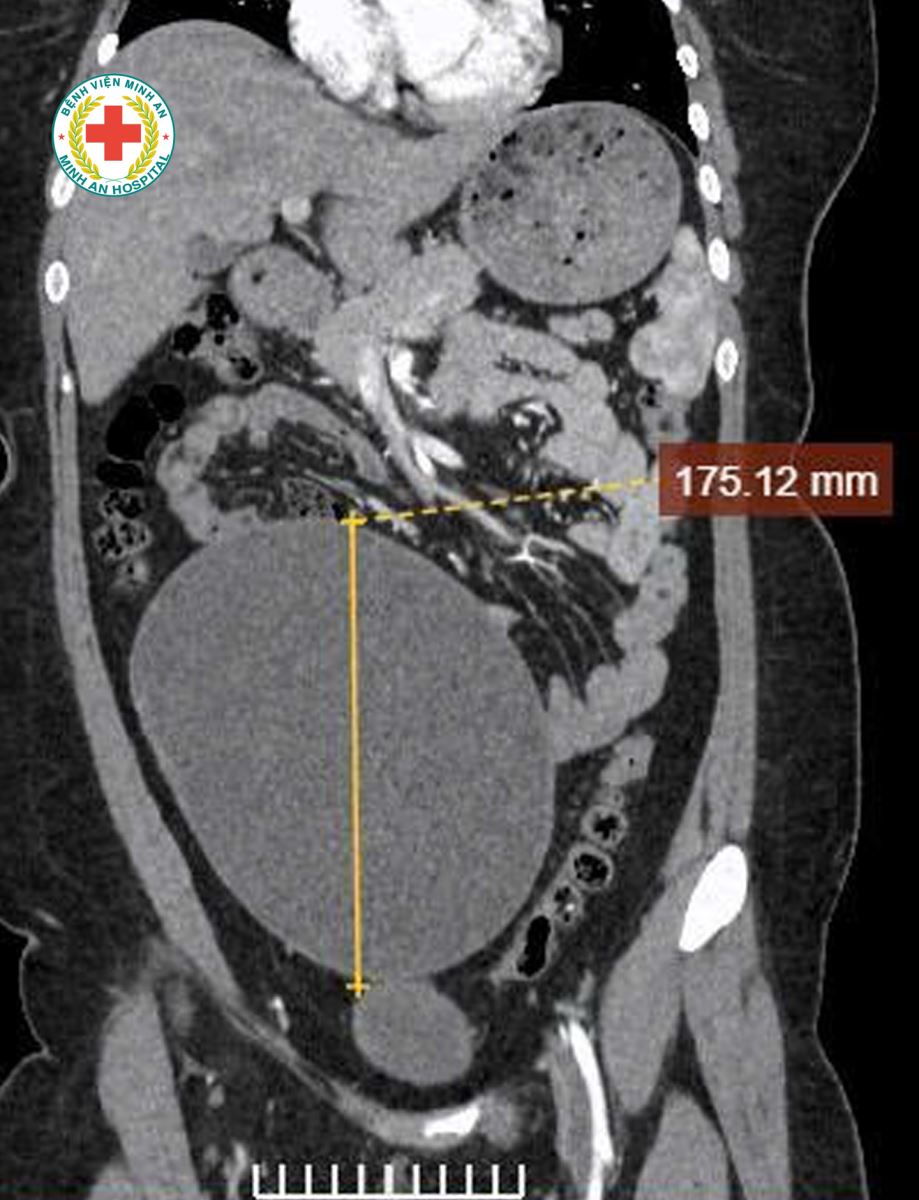

Khoa Sản – BVĐK Minh An vừa tiếp nhận tiếp nhận một trường hợp đặc biệt: U nang buồng trứng kích thước rất lớn, tương đương thai khoảng 20 tuần tuổi, người bệnh gần như không có triệu chứng rõ ràng, chỉ xuất hiện ra máu bất thường ngoài chu kỳ. Điều đáng chú ý là bênh nhân mới 22t, chưa từng sinh nở.